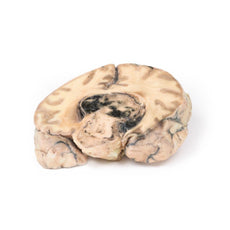

3D Printed Ruptured Berry Aneurism

Pathology

The specimen shows the basal surface of the brain. There is a saccular aneurism 5 mm in diameter at

the junction of the right internal carotid and the posterior communicating artery, which has ruptured. There is

subarachnoid blood in the immediate area in the cisterna magna and on the inferior surface of the right frontal

lobe. There is a similar unruptured aneurysm on the left side. The right frontal lobe appears softer and more

friable anteriorly